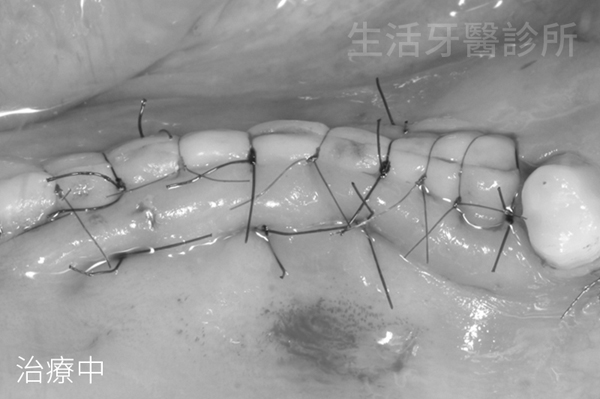

縫合術區,手術完成